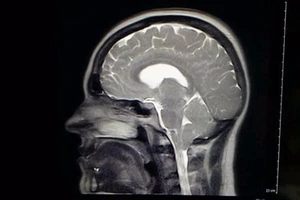

Không dám cười to vì sợ... thủng màng não